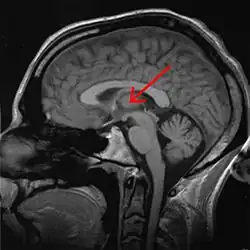

Encéfalo humano mostrando la ubicación del tálamo en una RMN. Pinchado flecha roja.

El núcleo reuniens es un componente del grupo nuclear medio del tálamo. En los mamíferos, está situado en la adhesión intertalámica (masa intermedia del tálamo).[1]